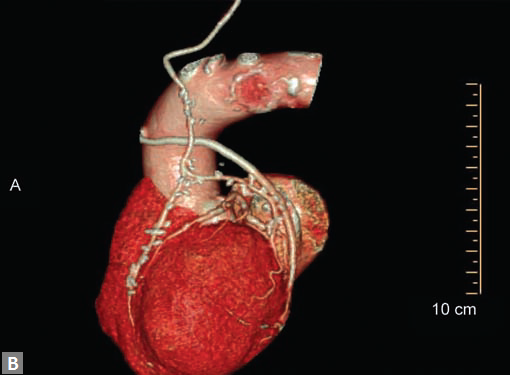

In the same sitting, ascending aorta can be assessed for

significant calcified plaques (Fig. 8B). This is an important

finding when coronary artery bypass graft (CABG) is

contemplated. Similarly, whenever required LIMA and right

internal mammary artery (RIMA) can be assessed in the same

sitting.

CT is the preferred tool of investigation of coronary bypass grafts (Fig. 9). Reversed saphenous vein grafts (SVGs) are optimally studied consistently. Anastomotic sites are studied effectively. However, distal anastomosis of venous graft to obtuse marginal branch (OM) is relatively difficult to evaluate because of diminishing caliber of native vessel. Arterial grafts pose a small challenge due to artifacts of associated surgical clips (Figs 10A and B). Ostium and proximal part of graft are assessed well. However, distal anastomotic site may be difficult to assess on occasions. RIMA graft, posterior descending artery (PDA) graft, gastroepiploic artery graft can also be studied. Stenosed venous grafts